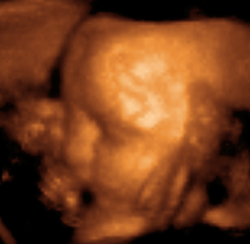

Head of a fetus, aged 29 weeks, in a "3D ultrasound"

The potential for ultrasonic imaging of objects, with a 3 GHz sound wave producing resolution comparable to an optical image, was recognized by Sokolov in 1939, but techniques of the time produced relatively low-contrast images with poor sensitivity.[27] Ultrasonic imaging uses frequencies of 2 megahertz and higher; the shorter wavelength allows resolution of small internal details in structures and tissues. The power density is generally less than 1 watt per square centimetre to avoid heating and cavitation effects in the object under examination.[28] High and ultra high ultrasound waves are used in acoustic microscopy, with frequencies up to 4 gigahertz. Ultrasonic imaging applications include industrial nondestructive testing, quality control and medical uses.[27]